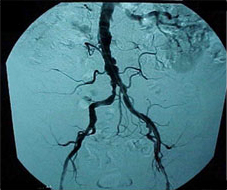

Embolization is a minimally invasive image guided technique to block or stop flow in blood vessels in order to bring therapeutic benefit to the patient. This technique is performed while the patient is conscious, but sedated and feeling no pain. It does not require general anesthesia. Further, there are many applications that allow for this technique to be employed in a wide variety of situations.

Embolization is especially useful in the treatment of tumors which rely on their blood supply to grow. The technique has brought therapy to millions of patients with tumors that are difficult or impossible to remove surgically.

The interventional radiologist makes a tiny nick in the skin in the groin and inserts a catheter into the femoral artery. Using real-time imaging, the physician guides the catheter through the artery and into the desired location. Contrast is injected to highlight the vessels for targeting. Multiple agents are available to facilitate the embolization. This allows for a tailored approach for each patient, allowing the greatest therapeutic benefit. Tumors can be embolized using synthetic materials called beads to deprive the tumors of blood. The beads most often have high doses of chemotherapy or radiation incorporated into them to most effectively treat the tumor. These treatments may also facilitate future surgical removal and cure once the tumors have shrunk.